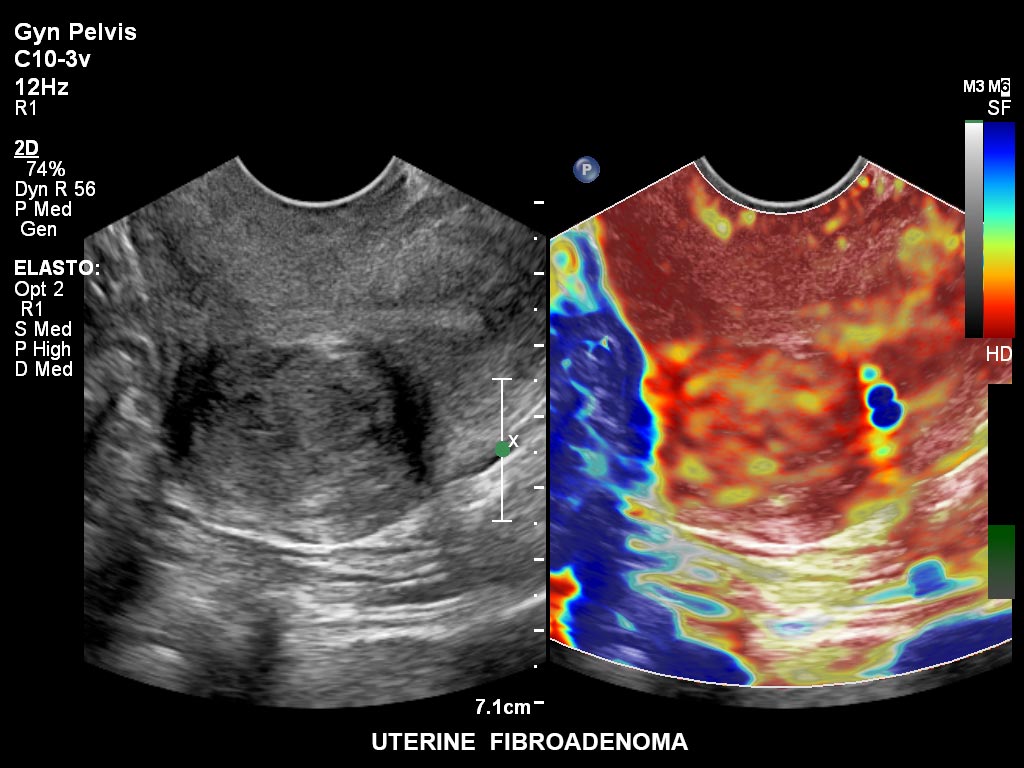

• C10-3v PureWave-Breitband-Endo-Convex-Schallkopf, ideal für anspruchsvolle Myom- und komplexe Ovar-Untersuchungen sowie Bildgebung im ersten Schwangerschaftstrimester